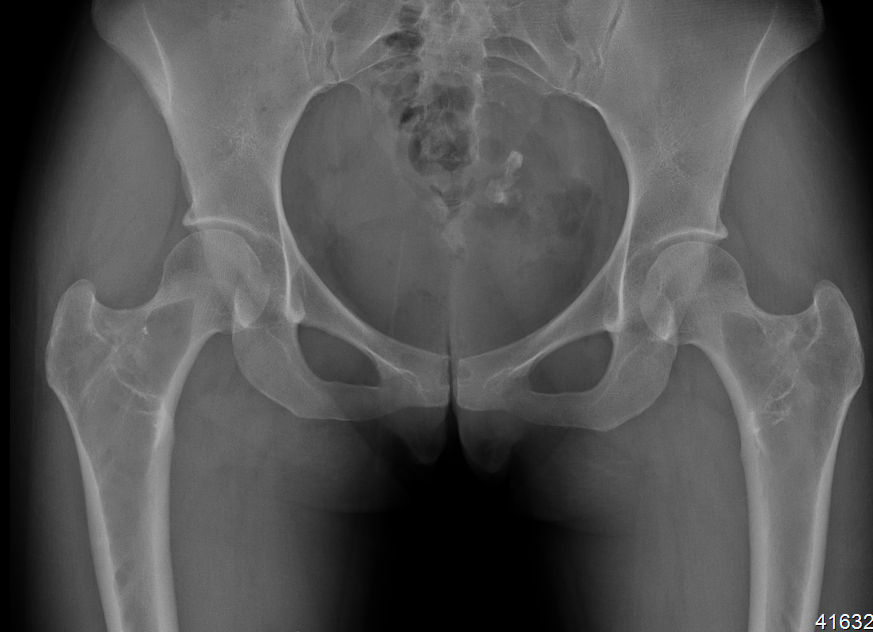

X-ray

Intramedullary lucent diaphyseal lesion with 'ground glass appearance'

- thinned, slightly bulged cortex

- ± endosteal scalloping

- may have angular deformity / bowing

Coxa vara and Shepherd's Crook deformity of proximal femur

- Shepherd's Crook - anterior bowing of femur

- secondary leg length discrepancy

- pain, difficulty walking